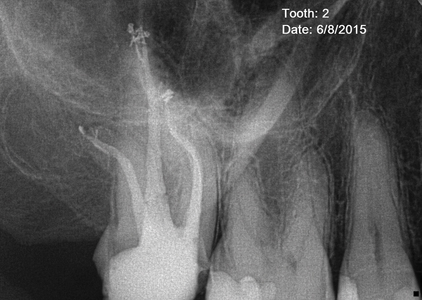

Agreeing to my definitions, I chose to survey 10 respected endodontists who have proofread my condensing of their answers and have selected pre- and post-treatment images that they believe radiographically represent their trenchant visual expression of the Endodontic Triad. (Fig. 2) Below, in alphabetical order, are their answers to my survey. Their techniques or armamentaria were copied and pasted from the survey, and where a quotable opinion was offered, it appears in quotes.

Fig. 2A

Fig. 2B

Fig. 2C

Fig. 2D

Fig. 2E

Fig. 2F

Fig. 2G

Fig. 2H

Fig. 2I

Fig. 2J

Fig. 2K

Fig. 2L

Fig. 2M

Fig. 2N

Fig. 2O

Fig. 2P

Fig. 2Q

Fig. 2R

Fig. 2S

Fig. 2T